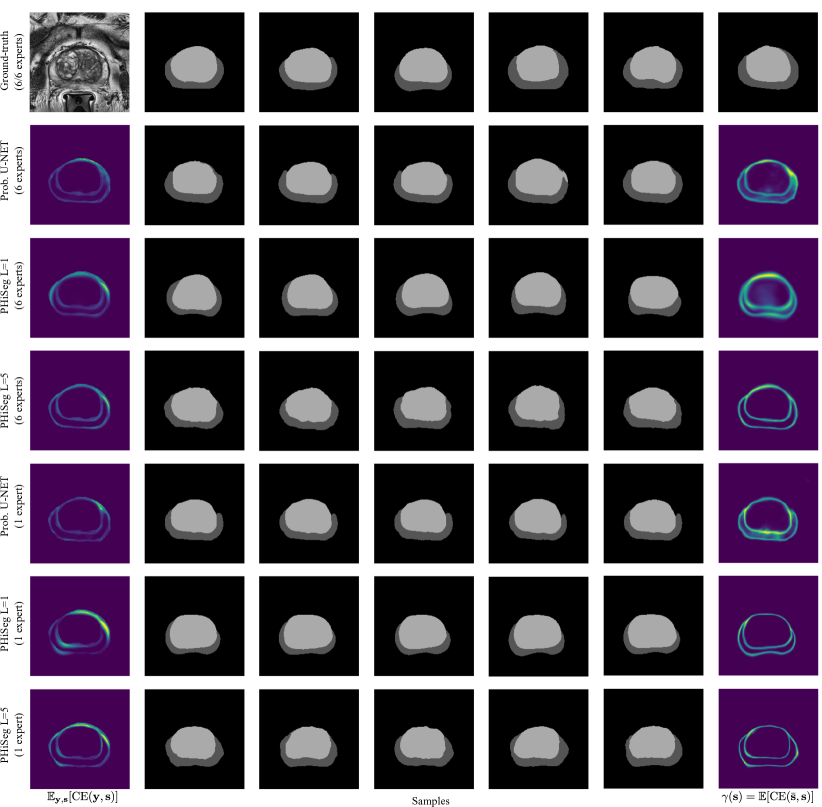

We evaluated the techniques in two experiments. First, we trained the methods using the masks from all available annotators, where in each batch we randomly sampled one annotation per image. We were interested in assessing how closely the distribution of generated samples matched the distribution of ground-truth annotations. To this end, we used the generalised energy distance where is 1 minus the intersection over union, i.e. , and are samples from the learned distribution , and ground-truth distribution [4]. The GED reduces the sample quality to a single, easy-to-understand number but, as a consequence, cannot be interpreted visually. Therefore, we additionally aimed to produce pixel-wise maps showing variability among the segmentation samples. We found the expected cross entropy between the mean segmentation mask and the samples to be a good measure, i.e. with the pixel position and the mean prediction. is statistically similar to variance with the L2-distance replaced by CE. However, we believe it is more suitable for measuring segmentation variability. Examples of our -maps along with sample segmentations are shown in Fig. 3. We quantify how well the -maps for each method predict regions with large uncertainty using the average normalised cross correlation (NCC) between the -maps and the CE error maps obtained with respect to each annotator:

We observed that when using all annotators for training, PHiSeg () produced significantly better and scores compared to all other methods. This can be observed qualitatively in Fig. 3 for a prostate slice with large inter-expert disagreements. Both, the prob. U-NET and PHiSeg () produced realistic samples but PHiSeg () was able to capture a wider variability. Furthermore, as indicated by the high values, PHiSeg’s () -maps were found to be very predictive of where in the image the method’s average prediction errors will occur. Similar results were obtained when training with only one annotator. We noticed that in this scenario the prob. U-NET may in some cases fail to learn variation in the data and revert back to an almost entirely deterministic behaviour (see fourth row in Fig. 3). We believe this can be explained by the prob. U-NET’s architecture which, in contrast to our method, allows the encoder-decoder structure to bypass the stochasticity. While our method also predicted smaller variations in the samples, they were still markedly more diverse. The lower performance of PhiSeg () indicates that using multiple resolution levels is crucial for our method. More samples for the prostate and LIDC-IDRI datasets can be found in Appendix B. From Tab. 1 it can be seen that no significant differences between the Dice scores were found for any of the methods (except PHiSeg’s ()), including the det. U-NET. From this we conclude that neither PhiSeg () nor the prob. U-NET suffer in segmentation performance due to their stochastic elements.

Appendix 0.B Additional Samples

Fig. 3 in the main article shows examples for a prostate with large inter-expert disagreements. In contrast, Fig. 0.B.1 is showing an example where the annotation disagreements were relatively smaller.